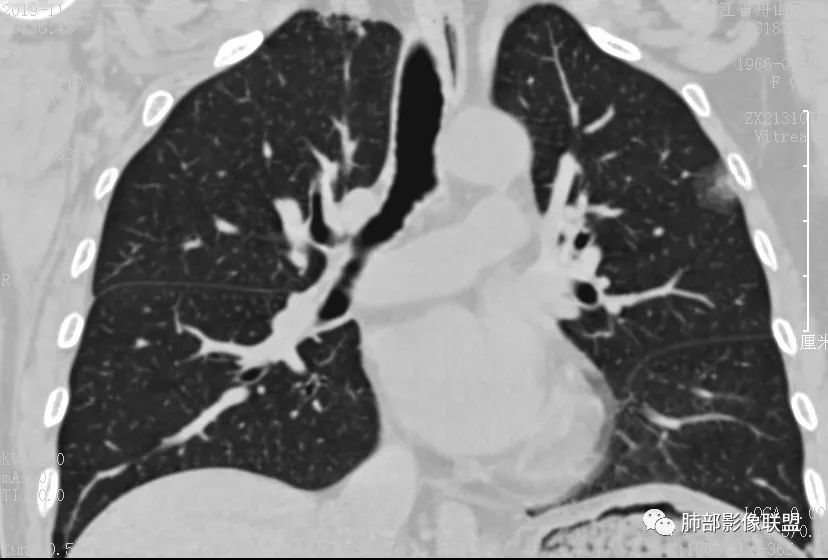

case3

男 29 医学百科网 | YxBaike.Com

开始讨论

Clover: 医学百科网 | YxBaike.Com

原位伴肺泡塌陷 医学百科网 | YxBaike.Com

右肺下叶磨玻璃结节,边缘清晰,中央肺泡塌陷,ais 医学百科网 | YxBaike.Com

PGG0,为AlS 医学百科网 | YxBaike.Com

右肺下叶血管旁混合磨玻璃,实性边界清晰,考虑AIS伴有肺泡塌陷。 医学百科网 | YxBaike.Com

MIA并肺泡塌陷或者AIS,大小目测大于6mm

应该是小于1CM,目测

AIS或MIA并肺泡塌陷 医学百科网 | YxBaike.Com

病理诊断 :

MIA

我觉得有中央肺泡塌陷,是比较轻的MIA 没看病理切片 肯定有塌陷

一句话小结:

血管旁磨玻璃小结节影,边界如此清晰,足以使人高度警惕! 医学百科网 | YxBaike.Com

中央显示有较清楚结节样实性密度区至少应想到微浸润腺癌的可能性。